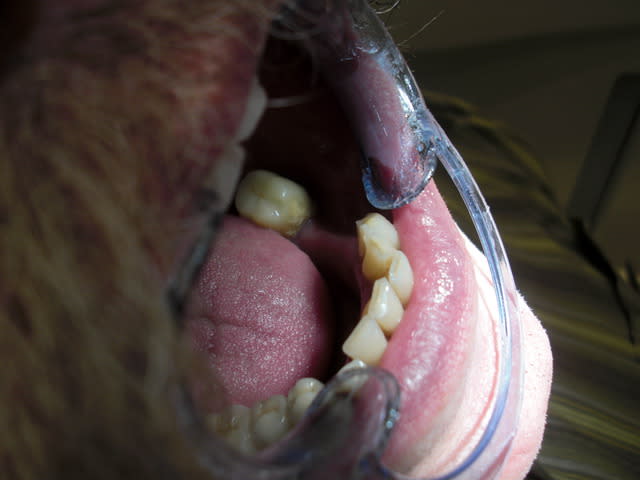

et là !

Image8 qjk3fn - Eugenol

si le sujet c'est l'implant c'est correct, si c'est le guide c'est flou...

par contre bravo pas de sang sur les gants